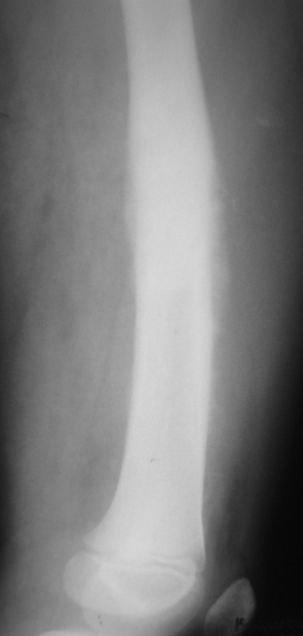

Мальчик 8 лет. Жалобы на боли в левом бедре. Со слов мальчика, ударился бедром несколько недель назад, после чего и начались боли.

В общем-то, диагноз сомнения не вызывает злокачественная опухоль, вероятнее всего - остеогенная саркома. У нас возникла дискуссия по поводу того, нужно ли брать открытую биопсию для гистологического подтверждения диагноза, либо сразу направить ребёнка в специализированный центр. С одной стороны, диагноз должен быть подтверждён гистологически. С другой - каждое нерадикальное вмешетельство на опухоли увеличивает вероятность метастазирования. В литературе чаще встречается такой подход - пациента сразу направляют в специализированный центр, где ему проводят как биопсию, так и дальнейшее лечение. Хотелось бы узнать мнение уважаемых коллег.

It could be Ewing sarcoma-its diaphyseal

Судя по представленным снимкам, нужно подумать о саркоме Юинга, так как Остеогенная саркома редко поражает диафиз трубчатых костей. Ее излюбленно место - метаэпифиз.